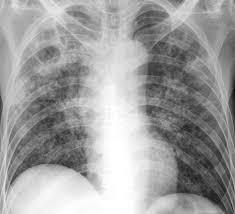

B.4 Korelasi klinis–radiologi–biologi

• TB primer: limfadenopati hiliar/mediastinal menonjol; efusi pleura dapat muncul 3– 6 bulan pascainfeksi (reaksi hipersensitivitas terhadap tuberkuloprotein; biasanya unilateral).

• TB post-primer: lesi apikal, kavitasi, diseminasi bronkogenik; gejala lebih ‘klasik’ (batuk >2–3 minggu, demam, keringat malam, penurunan BB).

• Komplikasi: bronkolitiasis (ekstrusi nodus limfe terkalsifikasi ke bronkus), hemoptisis, bronkiektasis, empyema, aspergiloma.